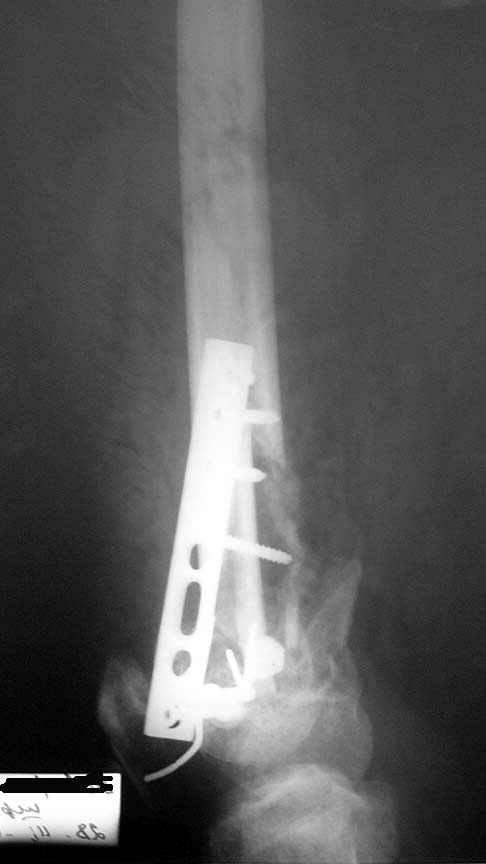

падение с высоты 7-го этажа, медсестра, молодая женщина 31 года.

падение с 7-го этажа 01 01 05. Молодая женщина 31 года,медсестра при падении с 7-го этажа получает только открытый многооскольчатый перелом метаэпифиза правого бедра. При поступлении удалены нежизнеспособные осколки,сформировался дефект кости. Выполнен остеосинтез из "того Что было" Раны зажили. Кокситная повязка. В которой наступило смещение отломков.Сейчас консолидация слабая,несостоятельность боковых связок коленного сустава, крестообразные связки держат. Кт для обследования нет. Что делать дальше-еще выжидать или пытаться активно помочь, и как?

А прямой снимок покажете? Без двух проекций ничего определенного не предложить.

Прошло 3 мес. после травмы. Движения в коленном суставе пробовали начать? Какая амплитуда сейчас? Как узнали, что это несостоятельность боковых связок, а не подвижность на уровне перелома?

А хотя бы вторая проекция? Хабаровск.